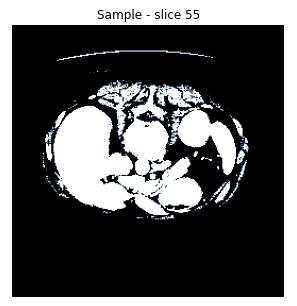

Each of these volumes is a DICOM file containing an arbitrary number of 512x512 images, with this number ranging from 75 to 624, and each of these images corresponds to a different vertical "slice" of the torso. The values of the pixels belong to the Hounsfield scale.

For example, let's visualize a slice (n. 55) from the first volume of the dataset: